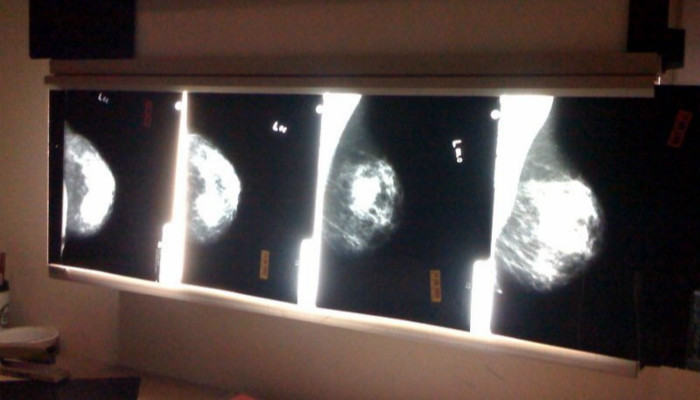

在太空的前三年,NASA的哈勃太空望远镜因为工程上的缺陷,拍摄了一些非常模糊的照片。这个问题在1993年修好之后,天文学家们又开始尝试利用早前的这些模糊的照片,他们用一个计算机算法从这些图片中提取信息。

最后这个算法被分享给了一为医生,这位医生把它用在了他正在探测乳腺癌的X射线图像上。这个算法在探测早前乳腺癌上比传统肉眼观察要实用很多。